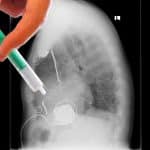

Un gran análisis liderado por el Centro Nacional de Investigaciones Cardiovasculares (CNIC), Fundación adscrita al Instituto de Salud Carlos III (ISCIII), realizada en colaboración con otras instituciones internacionales, ha reunido datos de 17.801 pacientes con infarto agudo de miocardio y función cardiaca normal incluidos en los 5 ensayos clínicos realizados en el mundo, y concluye que los fármacos betabloqueantes no aportan ningún beneficio clínico en este grupo de pacientes, que son la mayoría de los pacientes que superan un infarto hoy en día.

El estudio se ha publicado en la revista The New England Journal of Medicine (NEJM) y se presenta en el Congreso de la Asociación Americana del Corazón (AHA) en Nueva Orleans (EEUU). Los resultados reafirman las conclusiones del ensayo REBOOT, también liderado desde el CNIC-ISCIII; los betabloqueantes, uno de los tratamientos más extendidos tras un infarto agudo de miocardio, no reducen el riesgo de muerte, de nuevos infartos o de insuficiencia cardiaca en aquellos pacientes cuya función contráctil del corazón es normal.

Durante más de 40 años, todos los pacientes que sufrían un infarto eran tratados de por vida con betabloqueantes, independientemente de cómo estuviese la función de su corazón. Esto se debe a que los ensayos clínicos realizados en las últimas décadas del siglo pasado mostraron un beneficio de estos fármacos. Sin embargo, el manejo del infarto desde entonces ha cambiado radicalmente y el pronóstico de los pacientes es mucho mejor que entonces, y son menos propensos a tener arritmias malignas o insuficiencia cardiaca. Este metaanálisis confirma de manera irrefutable lo que ya apuntaba el Reboot los pacientes que tras un infarto que tienen una función cardiaca normal no obtienen ningún beneficio al ser tratados con betabloqueantes.